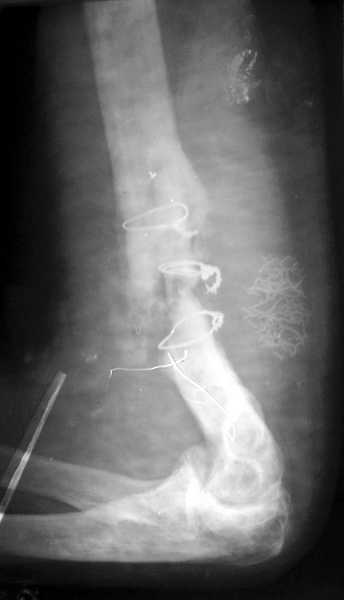

|

Уважаемый Алексей Минервин!

В подобном случае мы бы применили чрескостный остеосинтез. Пример - в приложении.

Всего наилучшего,

Л.Соломин